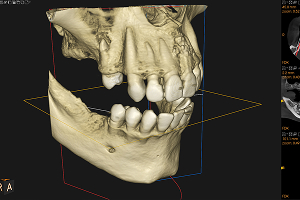

1.CT・セファロを用いた

精密診断

矯正治療を正確に進めるためには、骨格や歯の位置関係を詳細に把握することが欠かせません。そこで当院では、CT撮影やセファロ(頭部X線規格写真)を活用し、立体的かつ多角的な分析を行っています。CTでは歯や骨の構造を3Dで確認でき、セファロでは顎の角度や歯列のバランスを計測することが可能です。これらのデータをもとに、より精密で根拠に基づいた治療計画を立てています。